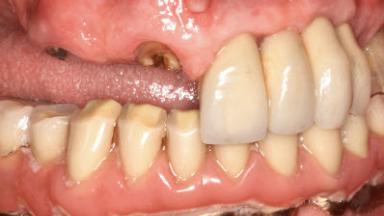

Retreatment of a Patient with Multiple Biological and Technical Complications and Failures

A 66-year-old patient presented because of retention loss of the tooth-supported FDP in the right maxilla (x-13-x-11). The mandibular full-arch implant-supported reconstruction (x-i34-i33-x-x-x-x-i43-i44-x) had suffered extreme wear. His medical history revealed high blood pressure, controlled with anti-hypertensive medication. The patient was a light smoker (2 to 3 cigarettes per day). The existing reconstructions had been performed alio loco about five years previously. That treatment had taken an extensive amount of time, and as early as during the fabrication of the reconstructions, multiple complications had occurred with the provisionals.

Prosthesis Type RDP